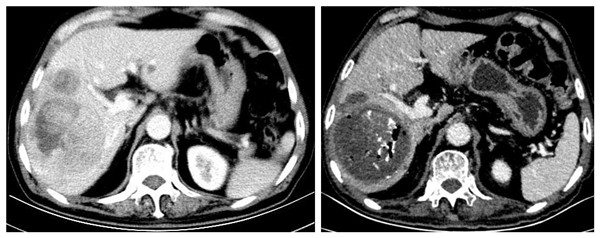

MDT讨论

TACE术前 TACE术后